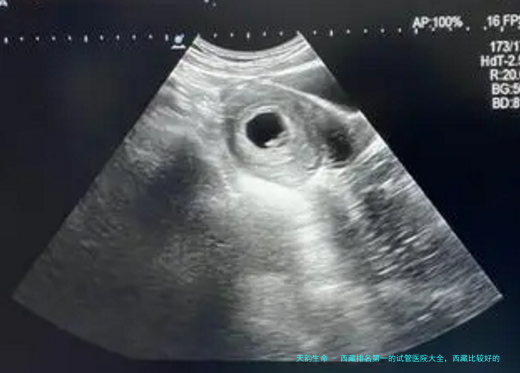

试管婴儿带来新生命

试管婴儿作为一种人类辅助生育技术,为试管婴儿助孕病患带来了新的盼望和新的生命。